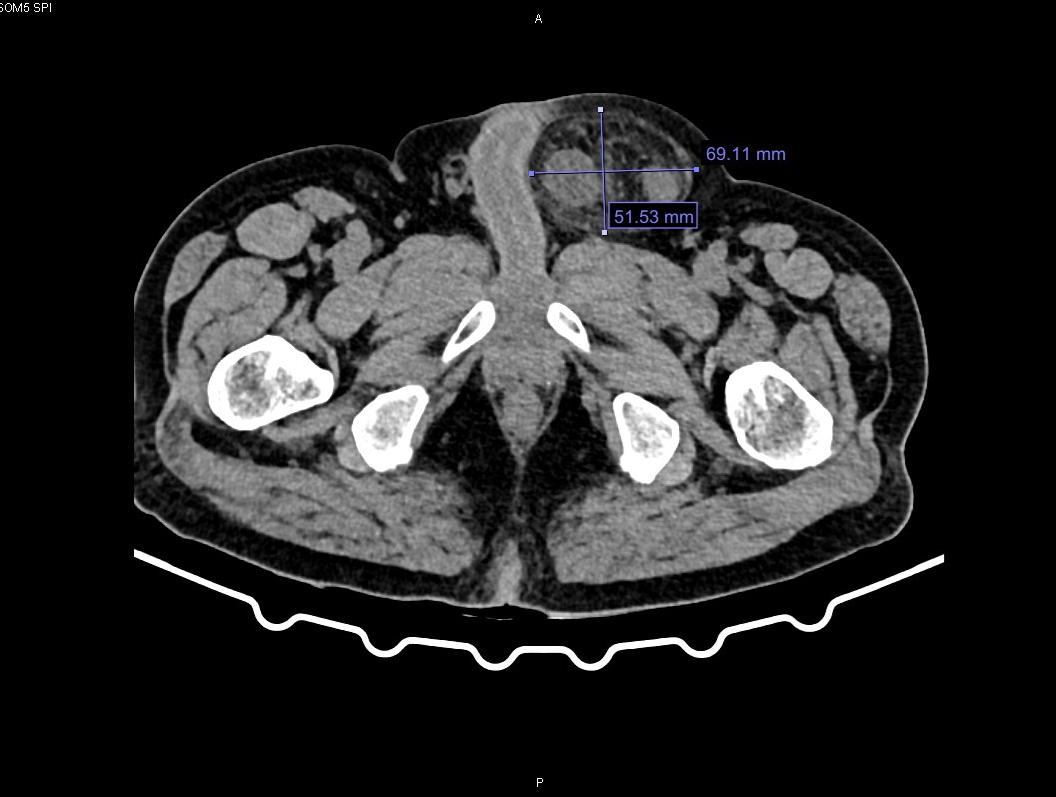

Hình ảnh khối thoát vị bẹn trái nghẹt qua phim chụp cắt lớp vi tính.

Sau khi thăm khám và chụp cắt lớp vi tính, các bác sĩ chẩn đoán bệnh nhân bị thoát vị bẹn trái nghẹt. Quá trình hội chẩn bác sĩ đánh giá, đây là biến chứng phức tạp, nguy hiểm của thoát vị bẹn do ruột bị chui xuống lỗ thoát vị và kẹt lại gây tắc nghẽn, thiếu máu nuôi. Sau đó, bệnh nhân được chỉ định mổ cấp cứu bằng phương pháp nội soi, nhằm giải phóng khối thoát vị và xử trí tổn thương.